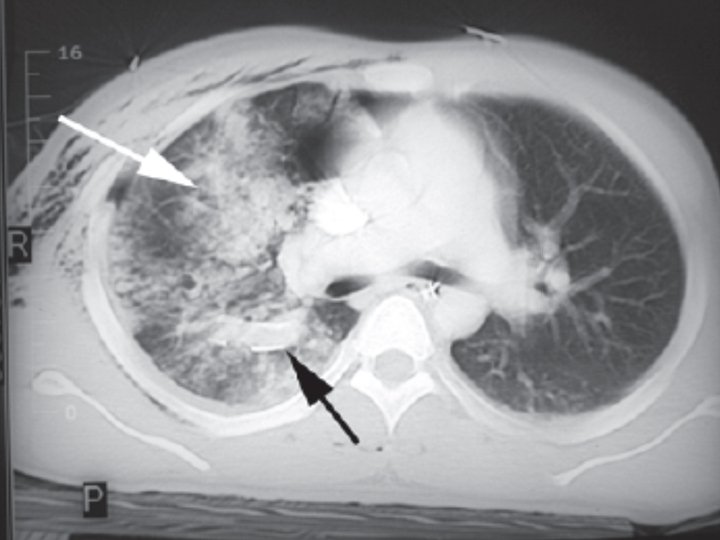

C. PULMONER KONTÜZYON • En yaygın letal göğüs yaralanması • Respiratuvar yetmezlik yavaş gelişebilir ve fark edilmesi güç olabilir. • Belirgin hipoksisi olan hastalar (oda havasında Pa. O 2<65 mm. Hg veya Sa. O 2<%90) yaralanmadan sonraki ilk bir saat içinde entübe ve ventile edilmelidir. . • KOAH ve Böbrek Yetm. Entübasyon eşiği ↓↓ • Stabil hastalar entübe edilmeden izlenebilir. • Transfer edilecek hastalar entübe ve ventile edilmelidir.

PULMONER KONTÜZYON